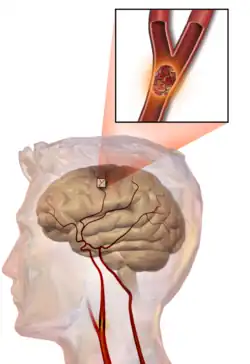

Thrombotic stroke

In thrombotic stroke, a thrombus[47] (blood clot) usually forms around atherosclerotic plaques. Since blockage of the artery is gradual, onset of symptomatic thrombotic stroke is slower than that of hemorrhagic stroke. A thrombus itself (even if it does not completely block the blood vessel) can lead to an embolic stroke (see below) if the thrombus breaks off and travels in the bloodstream, at which point it is called an embolus. Two types of thrombosis can cause stroke:

Embolic stroke

An embolic stroke refers to an arterial embolism (a blockage of an artery) by an embolus, a traveling particle or debris in the arterial bloodstream originating from elsewhere. An embolus is most frequently a thrombus, but it can also be a number of other substances including fat (e.g., from bone marrow in a broken bone), air, cancer cells or clumps of bacteria (usually from infectious endocarditis).[54]

Because an embolus arises from elsewhere, local therapy solves the problem only temporarily. Thus, the source of the embolus must be identified. Because the embolic blockage is sudden in onset, symptoms are usually maximal at the start. Also, symptoms may be transient as the embolus is partially resorbed and moves to a different location or dissipates altogether.